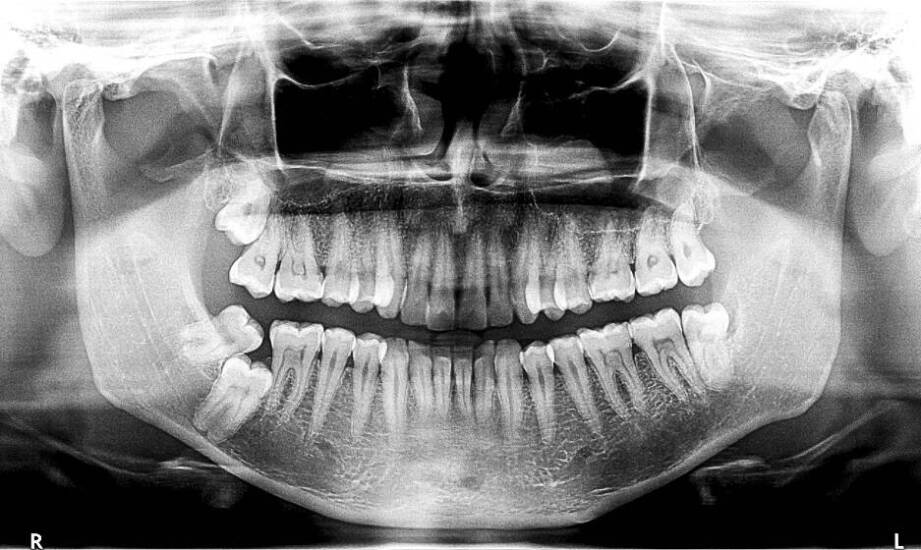

W stomatologii istnieje kilka rodzajów badań rentgenowskich, które różnią się między sobą zastosowaniem i techniką wykonywania. Najpopularniejsze to zdjęcia wewnątrzustne, panoramiczne oraz cefalometryczne. Zdjęcia wewnątrzustne umożliwiają dokładną analizę pojedynczych zębów oraz tkanek je otaczających, podczas gdy zdjęcia panoramiczne przedstawiają całe uzębienie oraz kości szczęk. Są one szczególnie przydatne w przypadku planowania leczenia ortodontycznego czy implantologicznego. Zdjęcia cefalometryczne stosowane są głównie w ortodoncji do analizy proporcji twarzy i ustawienia zębów. Każdy z tych typów badań ma swoje unikalne zastosowanie i pozwala na dokładną ocenę stanu uzębienia oraz tkanek otaczających, co jest niezbędne dla skutecznego planowania leczenia w stomatologii.